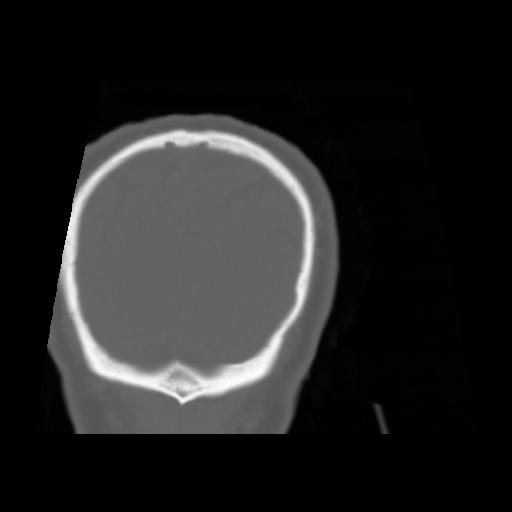

5 CEREBRO,,Coronal,3.000,CEREBRO,Coronal,